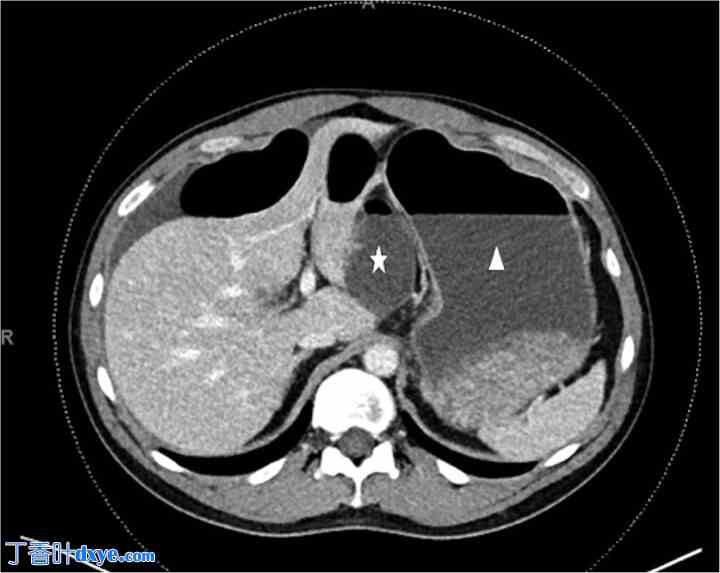

体格检查:患者生命体征稳定。腹部柔软、膨胀,全身压痛。实验室检查除白细胞计数升高至14外,未见异常。腹部CT扫描显示提示闭环小肠梗阻,疑似Winslow孔内疝(图1)。

图1

CT扫描。膨胀的胃(白色三角形)后方可见异常扩张且充满液体的小肠(白色星号)。